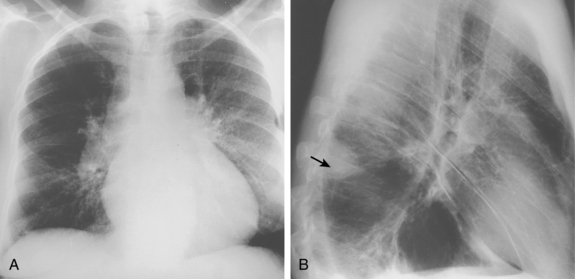

What’s the most significant finding in this CXR and what does it indicate?

Westermark Sign! = Pulmonary Embolus!